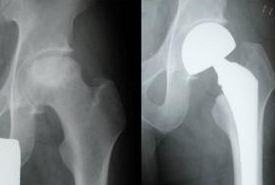

髋关节是人体负重的“核心枢纽”,而股骨头坏死作为中老年人高发…… 【详情】

股骨头坏死前期,骨骼尚未严重塌陷,但髋部疼痛、活动受限等症状已悄…… 【详情】